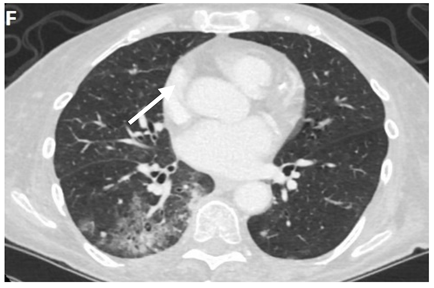

6.4.2. Chest CT-Scan

In the event of worsening symptoms after empirical antibiotics, Chest CT may provide more insights. Interestingly, the opacification lines in both X-ray and CT conform to radiation port rather than anatomical lines of lung structure, which could be diagnostic. Identified progression outside the lung field might suggest immune-mediated lymphocytic alveolitis [72]. Various stages of presentation provide different imaging outlooks (Table 3).

During the acute exudative stage, features of ground-glass attenuation or homogeneous consolidation may be noticed. A patchy consolidation that confirms the irradiation portal is also suggestive of the early phase. A discrete consolidation that conforms to the shape of the irradiation portal is proliferative changes of irradiation [71].

A chronic fibrosis stage with features of parenchymal distortion, traction bronchiectasis, and pleural thickening resulting in volume loss and irreversible changes are noticed. Refer to Table 2.